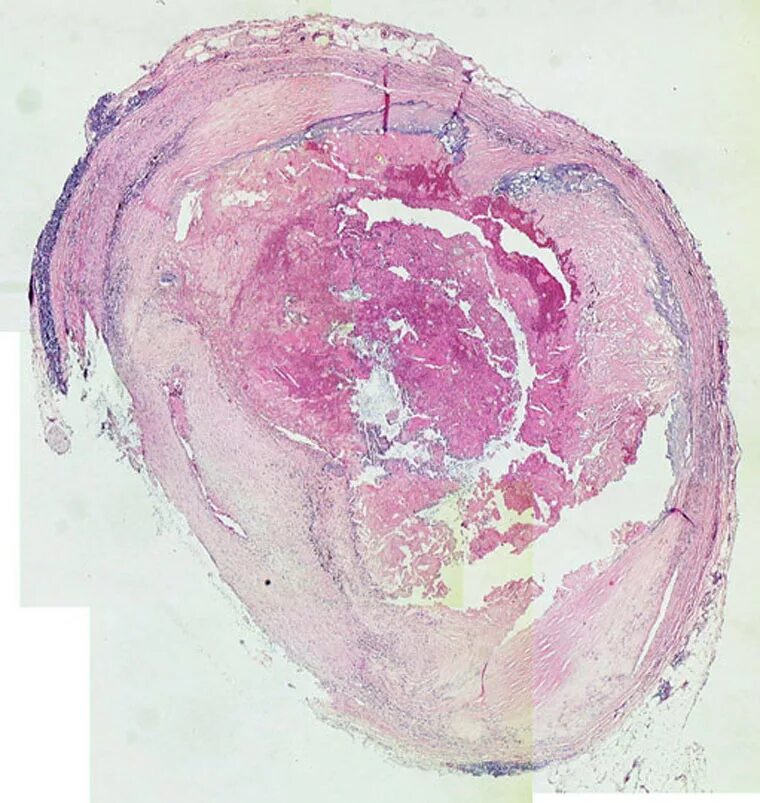

Гистология месяц